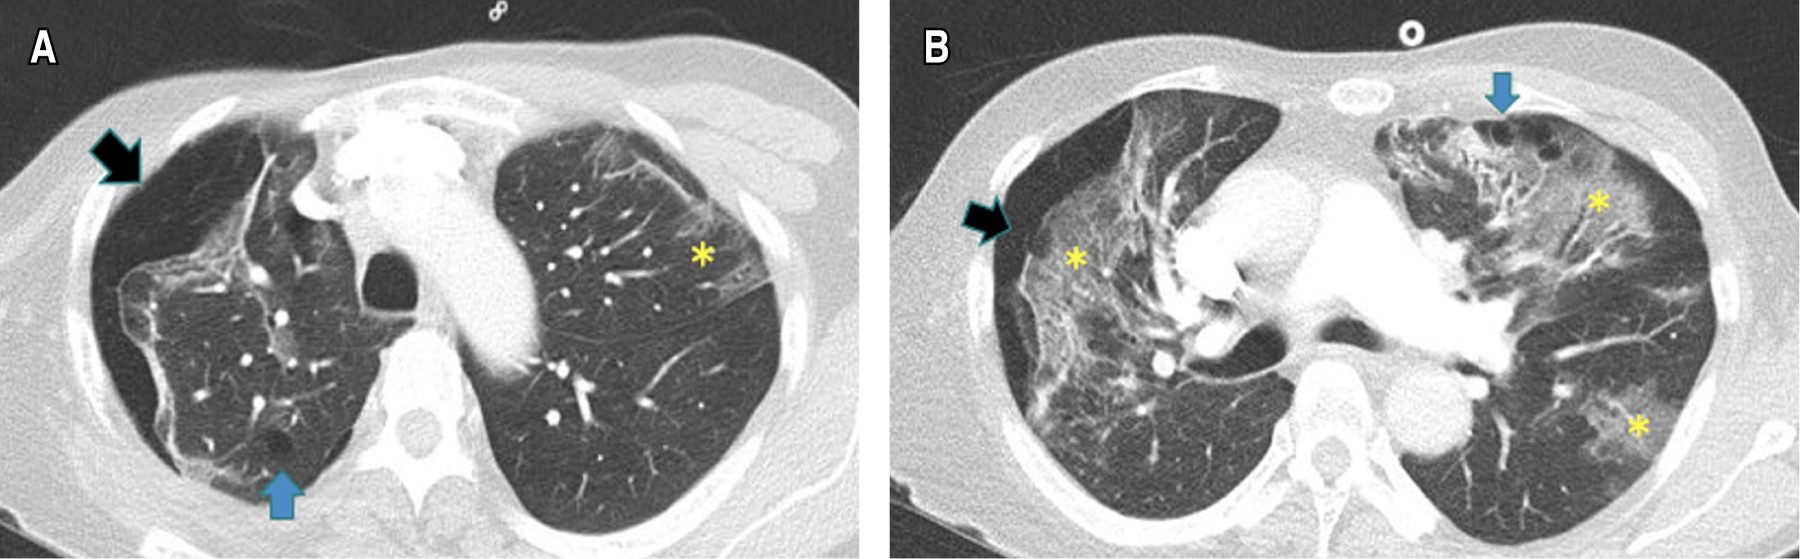

Caso 3. Masculino de 64 años, sin antecedentes relevantes ni tabaquismo. Ingreso hospitalario al día 11 de inicio de síntomas dados por disnea asociada a desaturación a medio ambiente (SaO2 85%), con confirmación molecular de infección por SARS-CoV-2 y radiografía de tórax con OVE difusas. El tratamiento inicial consistió en oxígeno (FiO2 32%), antipiréticos y dexametasona IV según el ensayo RECOVERY.20 Al día cuarto de estancia (día 15 de síntomas) presentó tos persistente, mayor deterioro del patrón respiratorio e hipoxemia severa sin mejoría con máscara de no reinhalación (FiO2 90%), ni pronación, además presencia de crepitaciones cervicales izquierdas. Paraclínicos con leucocitosis (16,600 cel/μL), linfopenia (300 cel/cel/μL), elevación de la LDH (524 U/L), hiperferritinemia (4,519 ng/mL) y DD en 630 ng/mL. Requirió intubación orotraqueal y traslado a la UCI. Se consideró descartar complicaciones de la COVID-19, se realizó una angio-TC de tórax que mostró TEP agudo y neumomediastino con enfisema cervical izquierdo (Figura 4). Se indicó anticoagulación con heparina de bajo peso molecular (1 mg por kg cada 12 horas), antibióticos y VM. Se realizaron otros estudios como fibrobroncoscopia y endoscopia de vías digestivas altas sin evidenciar hallazgos anormales. Se consideró neumomediastino espontáneo asociado a neumonía severa por SARS-CoV-2. Cirugía de tórax optó por manejo conservador, con una evolución hacia la mejoría y egreso al día 40. A los tres meses se realizaron pruebas de función pulmonar con espirometría sugestiva de restricción y capacidad de monóxido de carbono (DLCO), moderadamente disminuida (Tabla 1). En la actualidad continúa en sesiones de rehabilitación pulmonar con mejoría de la disnea.